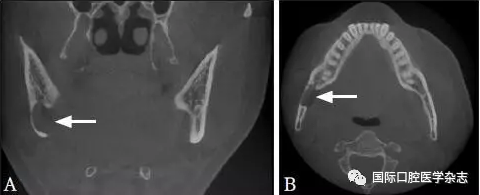

因拍攝角度的不同,頦孔和切牙孔影像可能與根尖重疊(圖8),應(yīng)注意觀察牙根的牙周膜及骨硬板是否連續(xù),或重新偏角拍攝X線片以確認其與牙根的關(guān)系。

圖 8 頦孔(A)和切牙孔(B)

Fig 8 Mental foramen(A) andincisive foramen(B)